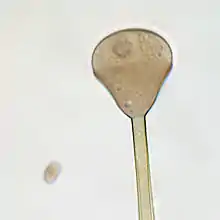

Apophysomyces variabilis resembles the other three members of the genus Apophysomyces but is characterized by the variable appearance of its sporangiospores and sporangiophores which range from club-shaped to trapezoidal to flattened spheres. The sporangiophore can measure up to 400 μm in length and has a funnel-shaped apophysis or swelling below the columella. Hyphae are smooth-walled, aseptate, and branched.[4]

Unlike most members of the Mucorales, Apophysomyces species often fail to sporulate under standard clinical laboratory culture conditions. These fungi require Czapek's agar (CZA), a nutrient-defined medium.[2] Colonies grow rapidly at 37 °C on CZA and initially appear white and woolly becoming greyish brown with age.[4][7][6] Colonies are grey and floccose, will grow on the lid of the petri dish, and are colourless on reverse.[8] Sporangiosphores are unbranched, smooth-walled, and light brown.[4] Sporangia are apophyseal, pyriform, beginning as whitish and turning brown with maturity. Sporangiospores are variable in size and shape.[7] Sexuality has not been observed in A. variabilis.[8]